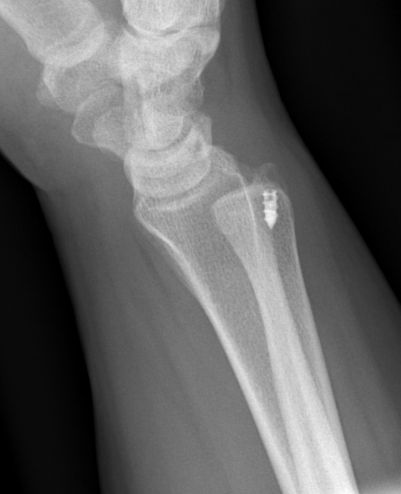

Isolated dorsal dislocation DRUJ

Isolated dorsal DRUJ instability with ulna sided TFCC tear

Xray

True lateral

- radial styloid overlies proximal scaphoid / lunate / triquetram

Dorsal subluxation of the distal ulna

CT